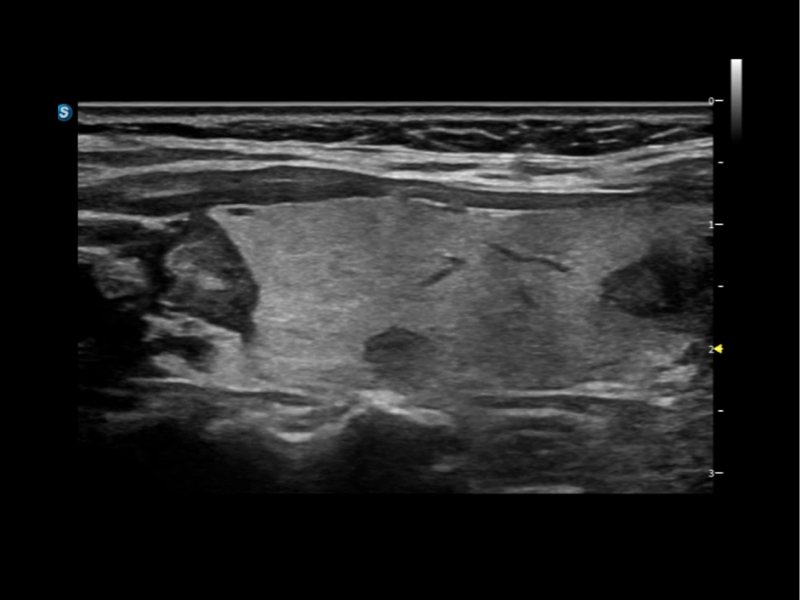

作为开立医疗全新打造的超高端旗舰超声产品,从探头抬起唤醒开启扫查到多维探头发射接收,通过先进的场成像发射、自适应聚合重建等技术,基于RF Data原始射频数据在图像生成、高端功能等方面实现突破,提供多科室综合临床解决方案。

独有场成像发射技术

自适应聚合重建技术